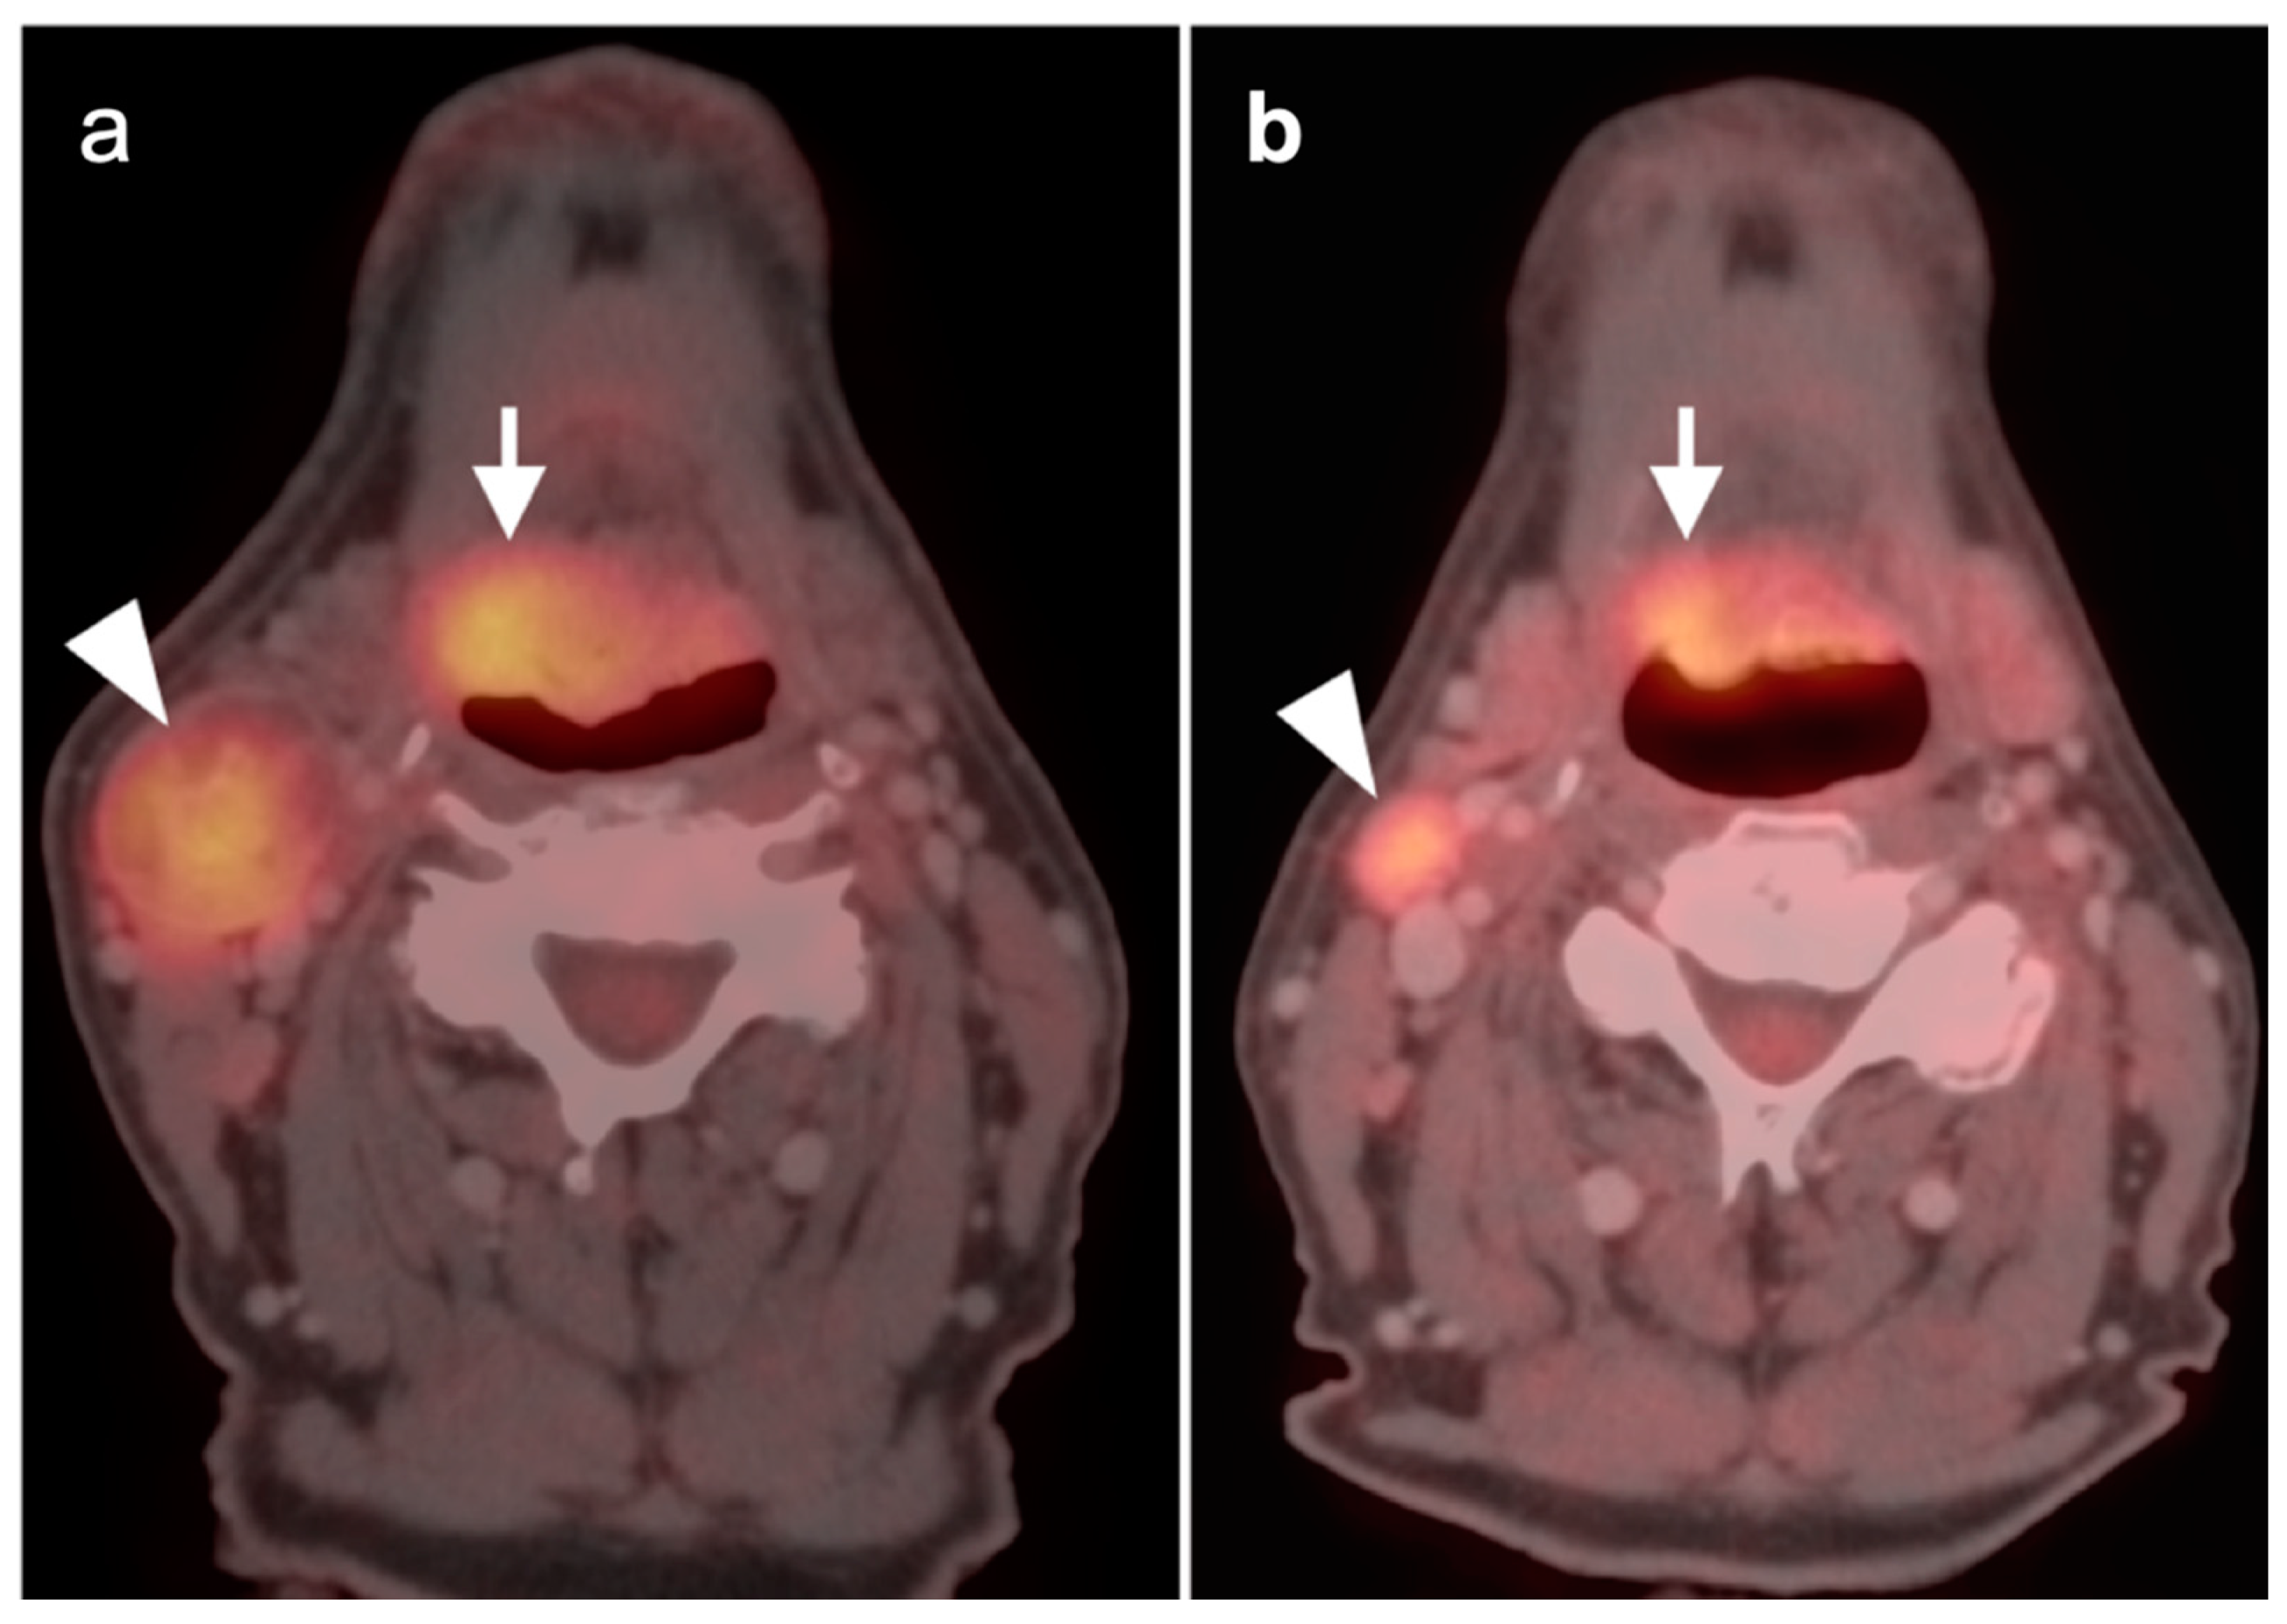

2.2. Squamous Cell Carcinoma of the Head and Neck (SCCHN)

- Oral cavity squamous cell carcinoma

- Oropharyngeal squamous cell carcinoma